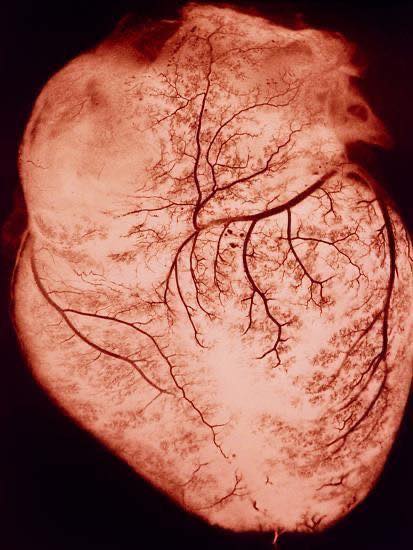

ออกกำลังกาย เร่งให้เลือดไหลเข้าระบบหลอดเลือดหัวใจแรงขึ้น ซ้อมให้ผนังหลอดเลือดรับรู้ถึงแรงของเลือด มันจึงวางแผนสร้าง ‘โรงงานสร้างก๊าซ nitric oxide’ (eNOS) เอาไว้เยอะๆ ทำให้หลอดเลือดหัวใจมีก๊าซนี้ คอยขยายหลอดเลือด คอยยับยั้งการเกิดลิ่มเลือดตอนช่วงวิกฤติไม่ให้ใหญ่มาก

แถมการไหลของเลือดที่มามากขึ้นนี้ ยังช่วยให้เกิดการแผ่ขยายเครือหลอดเลือดฝอยมากขึ้น เวลาอยู่ในช่วงวิกฤติ มีโอกาสสูงที่ตำแหน่งพื้นที่หลอดเลือดข้างเคียง ดันเลือดมาช่วยเลี้ยงได้ (Collateral circulation)